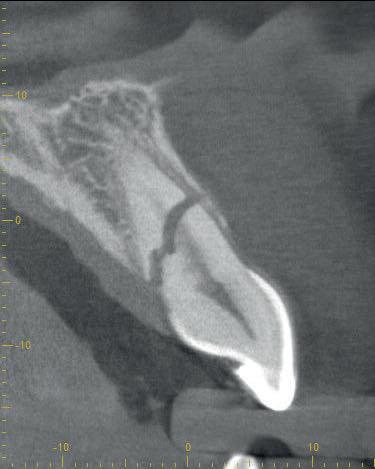

Casus

In deze casus is extractie van de 37 geïndiceerd in verband met een fistel en restpockets, zoals zichtbaar op de röntgenfoto’s (afbeelding 1). Duidelijk te zien is de forse peri-apicale ontsteking en het botverlies bij de 37, dat zowel richting buccaal als linguaal doorloopt. De 37 wordt atraumatisch verwijderd. Er is aan de linguale zijde veel bot verloren en er is sprake van een perforatie aan de buccale zijde.

Er wordt besloten om botmateriaal te plaatsen in de extractie-alveole. Vervolgens wordt het afgesloten met een titanium versterkt d-PTFE membraan (afbeelding 2). Na vier weken wordt het membraan verwijderd.

Zes maanden na extractie wordt het implantaat 37 geplaatst. Er is sprake van een goede genezing en de processushoogte en -breedte zijn behouden en opgebouwd. Ook is er zichtbaar gekeratiniseerd weefsel

gewonnen. De wond kan na het plaatsen van een healing abutment primair gesloten worden (Afbeelding 3a-3d).

In afbeeldingen 4a-c is het resultaat drie maanden na het plaatsen van het implantaat te zien. De genezing is volledig en de verwijzer kan de suprastructuur vervaardigen (afbeelding 4a-4c).

In afbeeldingen 5a-d is de implantaatkroon 37 te zien, twee jaar na plaatsing. Op de röntgenfoto is herstel van zowel corticaal als spongieus bot te zien. (De CB-CT was vervaardigd in verband met implantologische indicatie in het naastliggende gebied).